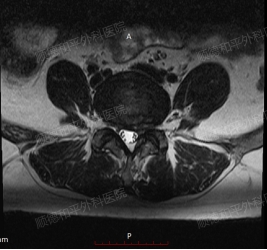

辅助检查:腰椎磁共振是重要的检查手段,可清晰显示椎间盘变性、膨出或突出,以及是否压迫硬脊膜囊、椎管、侧隐窝及椎间孔等。李女士的腰椎磁共振显示L4/5、L5/S1椎间盘存在变性、膨出并突出,且有相应的压迫情况,为诊断提供了有力依据。

患者为50岁中年女性,长期从事重体力劳动,因“左下肢疼痛麻木2月,加重1周”入院。查体见腰椎活动受限,左下肢沿坐骨神经走行区域(大腿后侧、小腿后侧及足底)压痛及感觉麻木。腰椎MRI显示L4/5左旁中央型及L5/S1中央型椎间盘突出,伴椎管及侧隐窝狭窄(左侧为著)。诊断为:腰椎间盘突出伴坐骨神经痛。经保守治疗无效后,由我院骨科二区(脊柱外科)张哉炯主任团队行经皮后路椎间孔镜下L4/5椎间盘髓核射频摘除术。术后患者症状显著缓解,恢复良好。